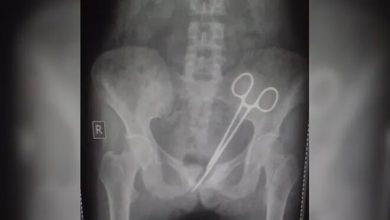

ڈاکٹر، مریضہ کے پیٹ میں قینچی بھول گئے، 12 برس بعد انکشاف

انڈین ریاست سکم میں ایک خاتون نے مسلسل رہنے والی تکلیف سے نجات کے لیے اپینڈکس کا آپریشن کروایا، لیکن…